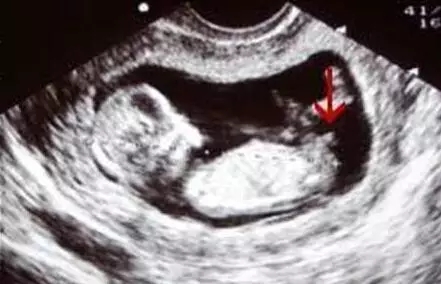

B超图分辨男宝女宝性器官

2017生男生女计算器

在照B超的时候,医生都会从屁股底下照看看左右的大腿,仔细观察的话可以发现在图中会有“谜之小凸起”,上图中的箭头所指就是,看到这里相信不用我说各位也一定看出来是一位小王子了。